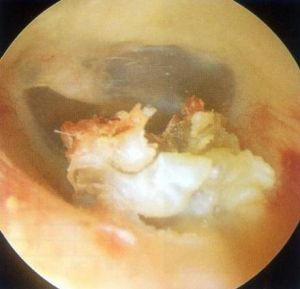

檢查時可以見到外耳道內有灰白色或者黃色角蛋白碎屑、上皮樣物堵塞,表面被多層鱗片狀物包裹,外耳道皮膚充血、腫脹、糜爛,可伴有肉芽形成。較大的膽脂瘤清除後可以見到外耳道的骨質暴露,被破壞、吸收,外耳道骨段明顯擴大,軟骨段一般無明顯改變。鼓膜一般是完整的,或充血,內陷,如果被膽脂瘤破壞,則會導致穿孔、萎縮和粘連。

外耳道膽脂瘤 外耳道膽脂瘤多見於30歲以上的成年人,主要表現為單側慢性鈍性耳痛,同時伴耳漏,分泌物有特殊臭味。肉芽形成時,還可以有膿血性耳漏。聽力減退者罕見。可見典型的灰白色的角蛋白碎屑,外耳道皮膚糜爛,骨質暴露,死骨形成,骨性外耳道下壁或後壁常有骨質缺損。病變部位可見肉芽組織和惡臭的膿性分泌物。鼓膜完整。組織病理學檢查:外耳道膽脂瘤侵蝕骨性外耳道壁,形成腔狀或袋狀骨質缺損,腔內被覆復層鱗狀角化上皮。病變周圍有局限性充血和慢性炎性細胞浸潤。外耳道深部充滿角蛋白碎屑,排列鬆散無規則,內含死骨和膿性碎屑。鼓膜完整。